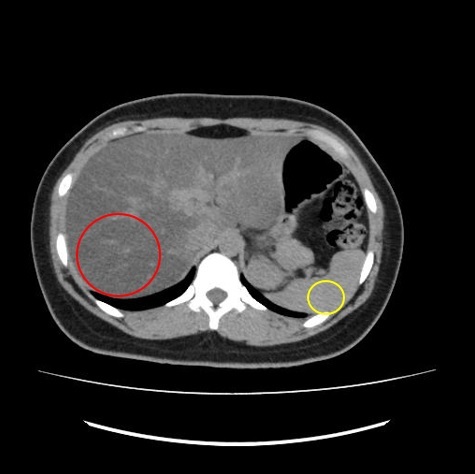

▼CT検査で得られる画像

例3 脂肪肝(脂肪が多くふくまれると黒く写る)

例4 胆石